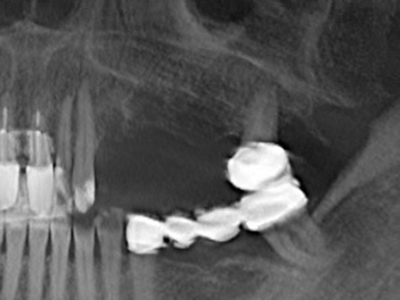

Фиг. 11: Следоперативната панорамна снимка показва вертикалната аугментация и синус лифта.

Препарацията на латерално ламбо по време на външен синус лифт е предизвикателство, особено за имплантолози с малък опит в хирургията. Отделянето на костното покритие на синуса без да бъде наранена лежащата отдолу Шнайдерова мембрана е само част от операцията – след установяване на подходящ достъп, линията на мембраната на синуса трябва внимателно да бъде повдигната, за да се направи място за материалите за аугментация или имплантите. Пиезохирургията е полезна за тази индикация по два начина: могат да се използват накрайници с диамантено покритие за избирателна костна аблация и едновременно с това, лежащата отдолу мукозна мембрана остава непокътната, когато процедурата е извършена прецизно. Ултразвуковите честоти също допринасят за отделяне на мукозната мембрана без усложнения – честотите се предават в пространството между мукозната мембрана и синуса чрез специални накрайници със заоблени ръбове (Cassetta, Ricci et al. 2012, Pereira, Gealh et al. 2014) (Rickert, Vissink et al. 2013). В резултат на това, не е изненадващо, че текущите доклади за външен синус лифт оценят положително пиезоелектрическите апарати, както и употребата на импланти с набраздени повърхности и костозаместителни материали. (Wallace, Tarnow et al. 2012).